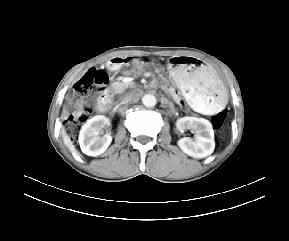

标题: CT19533:病变来源于哪?

患者,男,发现上腹部包块两月余。

病变位于肝胃间隙,实际就是位于小网膜囊(左肝下后间隙),呈轻度不均匀性强化,腹腔内及腹膜后见多发肿大淋巴结。所以我考虑肝胃间隙恶性胃肠间质瘤并淋巴结转移。

病灶强化不显著,灶周及腹膜后见多量淋巴结肿大,考虑淋巴瘤可能,其次考虑间质瘤

肝胃韧带内及腹膜后可见多发增大的淋巴结影,首先考虑转移.